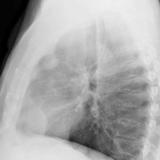

Thymoma

Date: 11/06/2013

Views: 3723